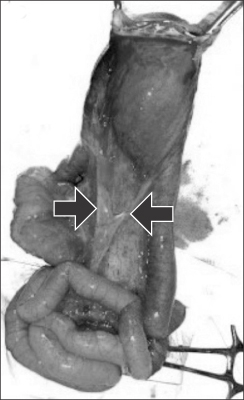

Fig. 2). The baby was taken up for surgery after adequate resuscitation. Intra-operatively, the sac contained few loops of small intestine. There was a fusiform SDI, about 25 cm proximal to the ileocecal valve. Note was made of conspicuous mesenteric vessels or mesenteric folds in a V-shaped pattern towards the two ends of the SDI (

Fig. 3). Resection and end to end anastomosis was done along with the abdominal wall repair. The child had an uneventful recovery and was discharged on postoperative day 7. The histopathology of the segment revealed normal ganglion cells and hypertrophy of muscle fibres.

The presence of mesenteric folds, abnormal mesenteric vessels demarcating the two ends of the dilated segment also suggest the presence of an erstwhile duplicated segment with its blood supply, which eventually got resorbed. This abnormal folds/vessel in the mesentery have been noted by some authors and is evident on some of the photographs in previous published articles [

45].

Fig. 3Intraoperative photograph shows segmental dilatation of the ileum (SDI). Black arrows depict the mesenteric bands/vessels in V-shaped pattern at ends of SDI.